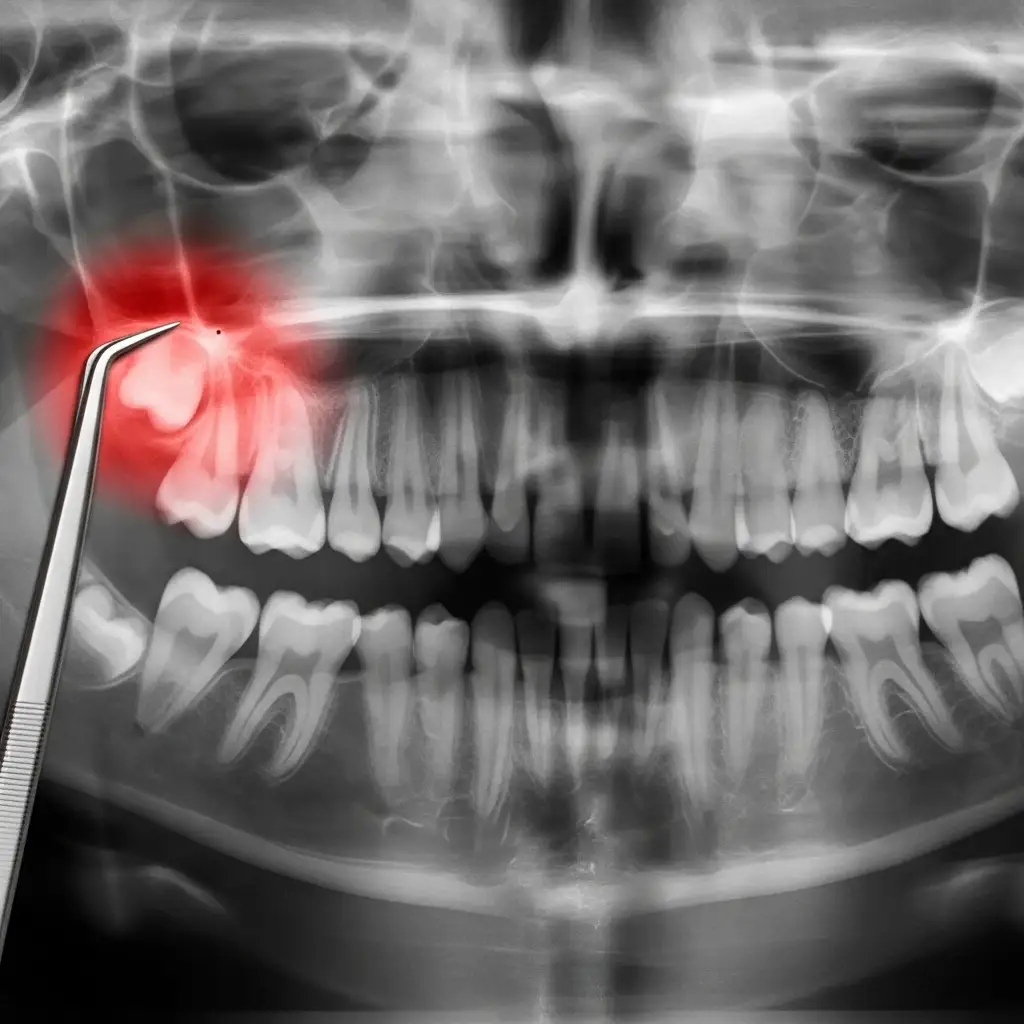

Comprehensive Assessment: Your first step is an evaluation with our team, including a panoramic X-ray to get a clear view of your wisdom teeth.

Informed Consent: We will review the X-ray with you, discuss the risks and benefits, and create a clear treatment plan.